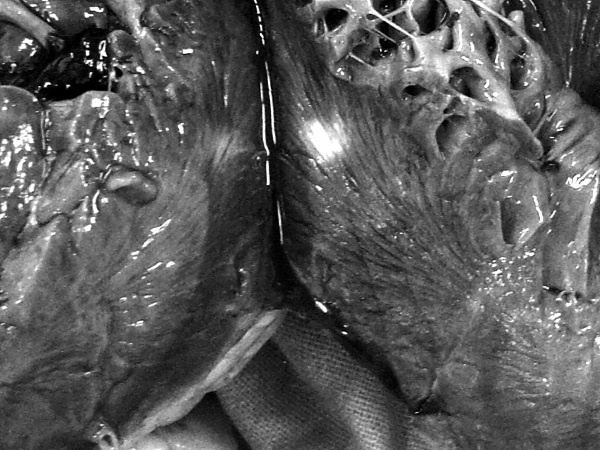

В посмертном эпикризе указан Основной диагноз: последствия ОНМК от 2008 года. ИБС. СН 2. ПИКС. Фоновое: СД 2-го типа, сопутствующее: хронический пиелонефрит. Осложнения: внебольничная пневмония. На секции: ![]() Рис. 31. Последствия перенесенного ОНМК ![]() Рис. 32. Атеросклероз церебральных артерий ![]() Рис. 33. Постинфарктный кардиосклероз ![]() Рис. 34. Гипертрофия миокарда левого желудочка ![]() Рис. 35. Признаки ХСН: мускатный фиброз печени ![]() Рис. 36. Пневмония ![]() Рис. 37. Признаки хронического пиелонефрита Анализируя данный клинический пример, необходимо отметить следующее. 1. Социальный статус. Социальный статус, за исключением указания на участие в ВОВ, не обозначен. 2. Наблюдение на дому. Полное несоблюдение регламента наблюдения ДИП. Клинический диагноз. Записи в амбулаторной карте нет. При этом диагноз должен быть следующим. Основной: последствия ОНМК от 2008 года. ИБС. Постинфарктный кардиосклероз. Фоновое: гипертоническая болезнь 3-й ст., 3 ст. риск 4. СД 2-го типа. Осложнения: длительная иммобилизация. Внебольничная пневмония. НК 2. Хронический пиелонефрит. Анемия. 3. Обоснованность назначения лекарственных препаратов. Терапия СД проводилась вне соответствия с клиническими рекомендациями, контроль за уровнем гликемии не осуществлялся, лечение анемии отсутствовало, вместе с тем при отсутствии подтвержденных данных за пиелонефрит были назначены антибиотики. Таким образом, наряду с указанными замечаниями врач не оценил тяжесть состояния, что не позволило решить вопрос о показанной госпитализации. Приложение № 6 – алгоритм лечения анемии. Приложение № 7 – самоконтроль уровня глюкозы. Пациентка Ф., 84 года. Умерла в январе 2011 года. Иммобилизирована с марта 2010 года в связи с закрытым переломом лонной и седалищной костей. В карте ежемесячные осмотры терапевта в связи с активами СМП. Причина вызовов: гипертонические кризы и болевой синдром. За год до смерти проведены доступные на дому анализы. В плановом порядке в апреле 2010 году проходила стационарное лечение в терапевтическом отделении. Диагноз при выписке: дисциркуляторная энцефалопатия 2-й ст. ГБ. ИБС. СН 3. ПИКС от 2001 года. Железодефицитная анемия. Закрытый перелом лонной и седалищной костей справа. Амбулаторно после стационара принимала энап Н и винпоцетин. В посмертном эпикризе указан Основной диагноз: 1) дисциркуляторная энцефалопатия 2-й ст. и ИБС. СН 3. ПИКС от 2001 г. НК 2А. Фоновое: ГБ. Сопутствующее: хроническая железодефицитная анемия. Закрытый перелом лонной и седалищной костей от 11.03.2010. ![]() Рис. 38. Повторный инфаркт головного мозга ![]() Рис. 39. Постинфарктный кардиосклероз ![]() Рис. 40. Атеросклероз коронарных артерий ![]() Рис. 41. Проявления НК: мускатный фиброз печени ![]() Рис. 42. Острые эрозии желудка ![]() Рис. 43. Атеросклероз аорты Замечания к ведению больного следующие: 1. Социальный статус. Информации нет. 2. Наблюдение на дому. Посещение терапевта осуществлялось только в связи с активами СМП. 3. Клинический диагноз. Нет правильной формулировки диагноза. При этом правильный диагноз был бы следующим. Основной диагноз: 1) Повторный инфаркт головного мозга. 2) ИБС. Постинфарктный кардиосклероз от 2001 года. Фоновое: гипертоническая болезнь 3 ст., 3 ст. Осложнения: закрытый перелом лонной и седалищной костей от 11.03.2010. Длительная иммобилизация. НК 2. Острые эрозии. Хроническая железодефицитная анемия. Сопутствующие: атеросклероз аорты. 4. Обоснованность назначения лекарственных препаратов: лекарственная монотерапия ГБ эналаприлом неэффективна, что повлекло за собой неоднократные гипертонические кризы и вызовы СМП, нет лечения проявлений ПИКС и анемии. Таким образом, не было оценки тяжести состояния, наличия тяжелой степени АГ у больной с перенесенным ОНМК и инфаркта миокарда, кризовым течением и признаками СН, что требовало госпитализации пациента. Приложение № 8 – ведение больного, перенесшего инфаркт миокарда. Пациентка Б., 95 лет. Иммобилизирована. Карта малоинформативна. Осмотры терапевта 1–2 раза в год, лист впервые выявленных диагнозов не ведется. Анализы отсутствуют. Известно, что наблюдалась с диагнозом ИБС, ЦВБ. Хронический бронхит. ОНМК с левосторонним гемипарезом и перелом шейки бедра без указания давности. В карте имеются указания на пролежни. За последние 2 года до смерти терапевтом были назначены: пирацетам, предуктал, мексидол, проведен курс ЛФК на дому. Посмертный эпикриз отсутствует. На секции: ![]() Рис. 44. Последствия перенесенного инфаркта головного мозга ![]() Рис. 45. Постинфарктный кардиосклероз |